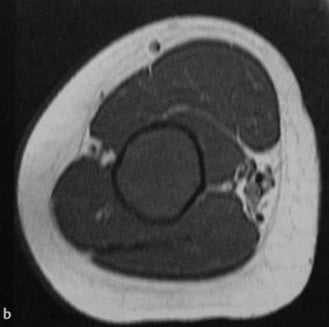

a-d Фиброзная дисплазия. Женщина 48 лет с фиброзной дисплазией, поражающей дистальный отдел плечевой кости: a) На рентгенограмме диафиза плечевой кости определяется кистозное географическое поражение с пузырным расширением. Типичное изображение в виде «битого стекла»;

b) Аксиальная Т1- взвешенная последовательность. Гипоинтенсивное поражение с истончением кортикального слоя.

c) Т2-взвешенная последовательность. Гипоинтенсивный сигнал по отношению к нормальной жировой ткани костного мозга;

d) Т1-взвешенная последовательность после введения гадолиния. Гомогенное на¬копление контрастного вещества в области поражения.